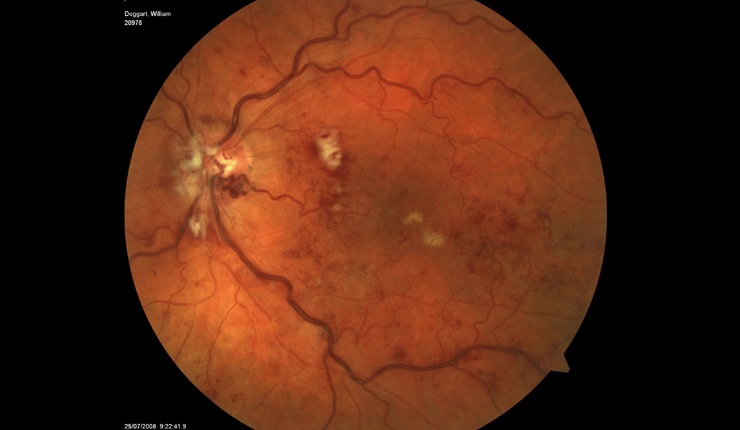

Highly reflective choroidal neovascular membrane (CNV) associated with AMD. Some residual fluid remaining at the interface of the CNV and outer retina.